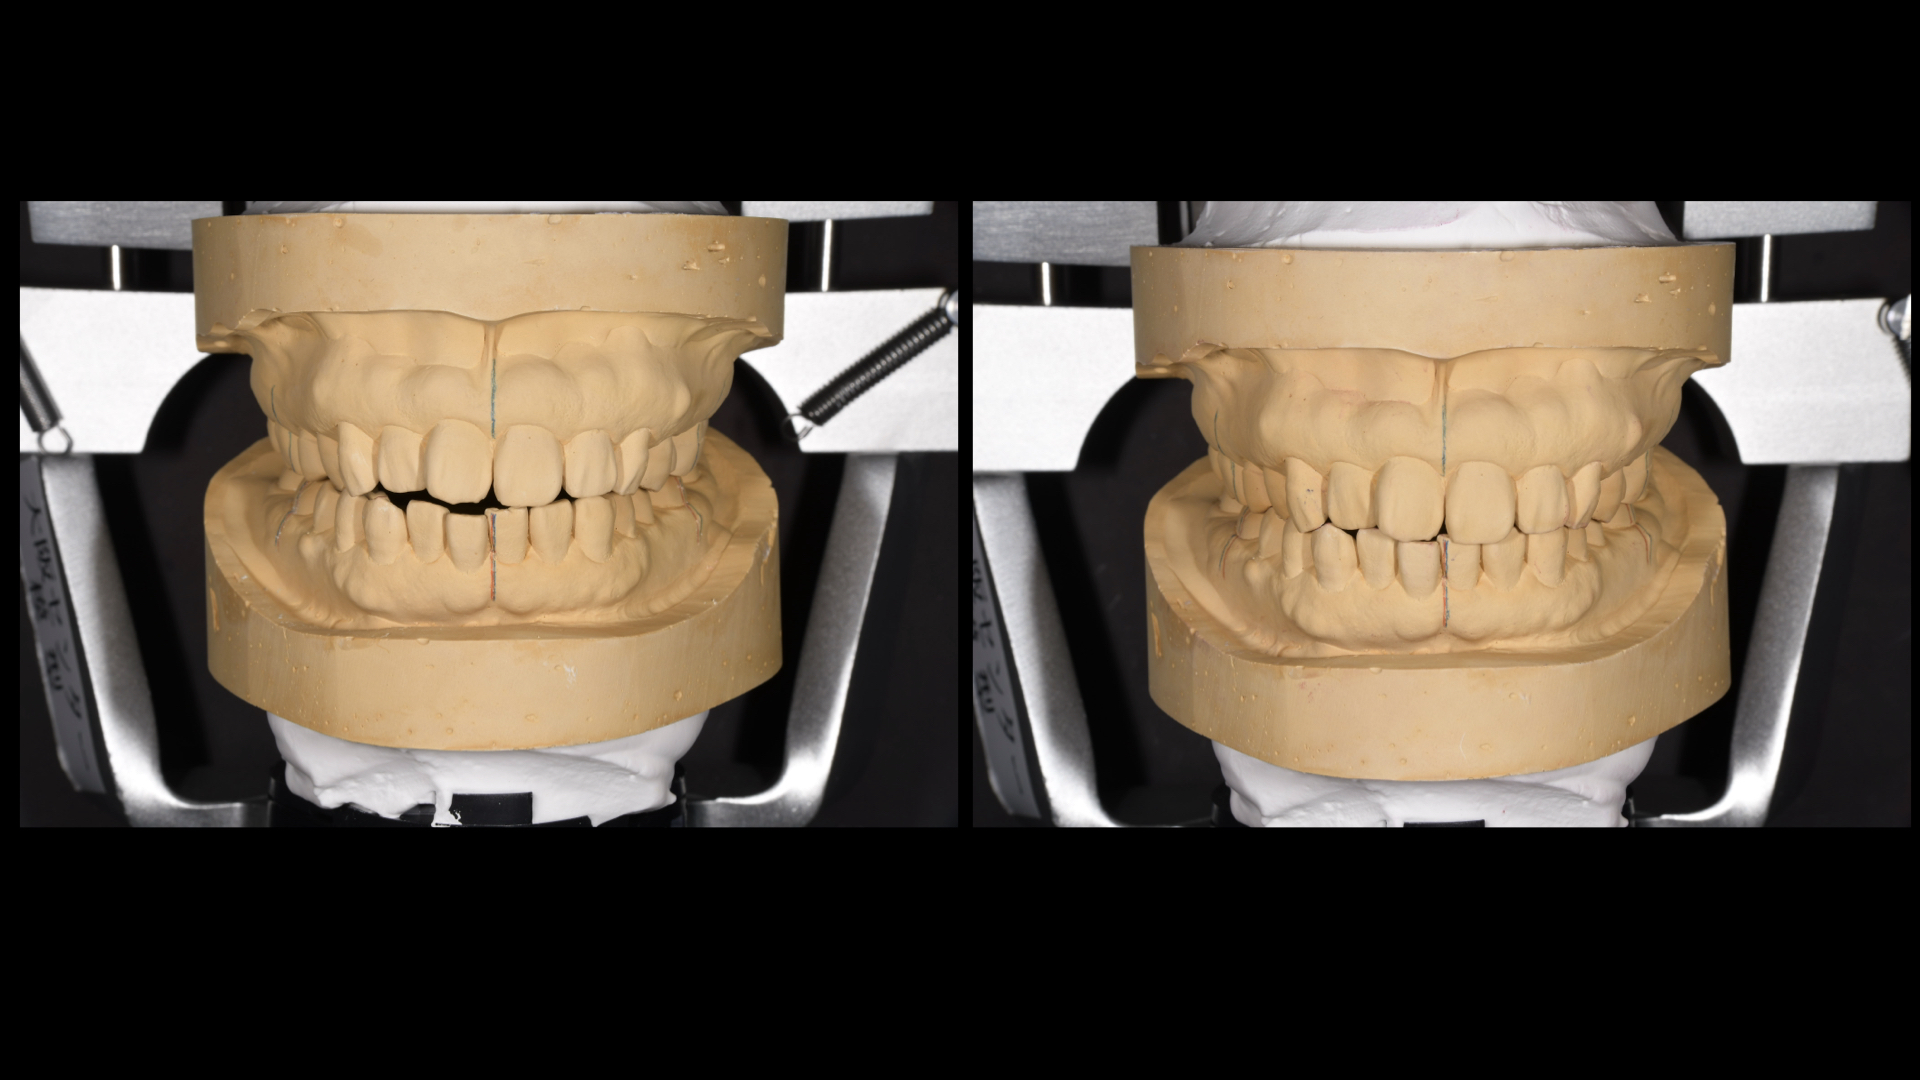

矯正の診断をおこないました。

そこで矯正をせずに前歯を噛ませるにはどうしたらよいか。模型上でシミュレーションをしました。

すると、茶色のwaxの部分は足しているところで、鉛筆の斜線は削っているところです。

下の前歯はほとんど足す必要があり、多くの歯を治療しなければいけません。

どうしても全体的な矯正治療(平均2〜3年)を望まれなかったので、模型上で咬合調整をおこない、やや前歯が噛み合うところまで調整すると矯正治療期間が短くなります。

模型上で、そこから歯を並べて(排列)みて奥歯をさわらずに短い期間で矯正治療ができるのかをシミュレーションした結果

可能ということがわかったので、この計画にしました。